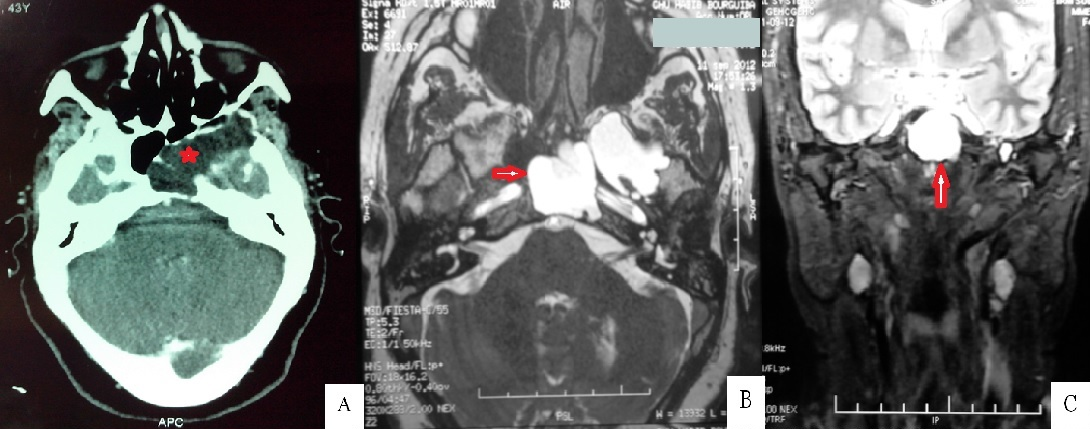

Il s'agissait d'une patiente âgée de 45 ans, sans antécédents de traumatisme crânien, qui a consulté pour des céphalées intermittentes isolées évoluant depuis le jeune âge. L'examen clinique était strictement normal. Le scanner cérébral a montré une lésion hypodense expansive ostéolytique du sinus sphénoïdal s'étendant vers la fosse infra-temporale en bas et la fosse temporale en haut (A). Cette masse ne prenait pas le produit de contraste. Une mucocèle a été suspectée et un complément par IRM a été réalisé. Cette dernière a montré que la masse avait le même signale que le LCR et en continuité avec la méninge temporale sans modification du parenchyme cérébral (B, C). Le diagnostic d'un kyste arachnoïdien a été retenu. Devant l'extension du kyste et l'absence de paralysie nerveuse, la décision était l'abstention thérapeutique et la surveillance clinique et radiologique. En conclision, les lésions kystiques étendues du sphénoïde sont relativement rares et peuvent provoquer des symptômes non spécifiques. Bien que ce soit une lésion très rare, le kyste arachnoïdien doit être présent à l'esprit. Le plus souvent, son diagnostic peut être déterminé à partir des données de la TDM couplée à l'IRM avec séquence de Diffusion, qui permettent le diagnostic différentiel avec les autres lésions, notamment avec une mucocèle.